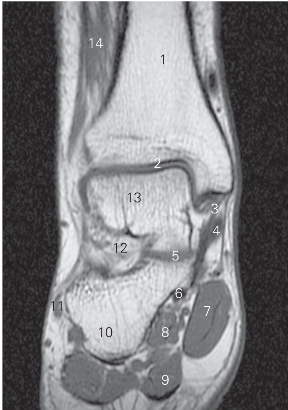

图5-47 经距骨颈的横断层MR T1加权图像

1 胫骨 tibia 2 踝关节 ankle joint

3 胫舟韧带 ligamenta tibionaviculare

4 胫骨后肌 tibialis posterior 5 舟骨 navicular bone

6

长屈肌 flexor hallucis longus 7

展肌 abductor hallucis

8 足底方肌 quadratus plantae 9 趾短屈肌 flexor digitorum brevis

10 腓骨短肌 peroneus brevis 11 跟骨 calcaneus

12 趾短伸肌 extensor digitorum brevis 13 距骨颈 neck of talus

14 腓骨短肌 peroneus brevis

15 趾长伸肌 extensor digitorum longus

图5-48 经距骨前份的横断层MR T1加权图像

1

长伸肌 extensor hallucis longus 2 距骨 talus

3 趾长屈肌 flexor digitorum longus 4

5

长屈肌 flexor hallucis longus 6 趾短屈肌 flexor digitorum brevis

7 小趾展肌 little toe abductor 8 足底方肌 quadratus plantae

9 腓骨短肌 peroneus brevis

10 趾长伸肌 extensor digitorum longus